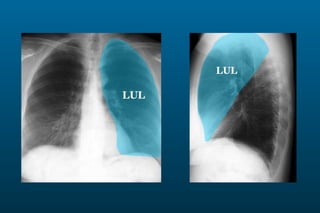

1) The posterior-anterior (PA) view is the standard and most reliable technique for a chest x-ray. It allows detection of air under the diaphragm. 2) A lateral view helps localize infiltrates and evaluate the cardiomediastinal silhouette, effusions, and left atrial dilation. 3) An anterior-posterior (AP) view is used when a patient is too ill to be transported, but image quality is poorer and structures may appear enlarged compared to a PA view.